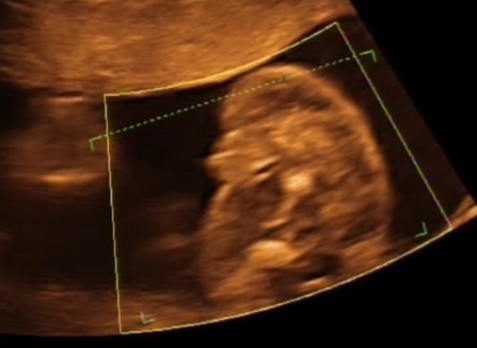

już nie wiem z tego wszystkiego) i dlatego przytulanek zakazała. Myślę tylko, że ona tak na zimne dmucha, bo praktycznie od samego początku nam zakazuje. To ma chyba związek z moim poronieniem. Bo jak byłam 1,5 tygodnia temu na połówkowym u innego gina to stwierdził, że łożysko ładne i nic nie mówił